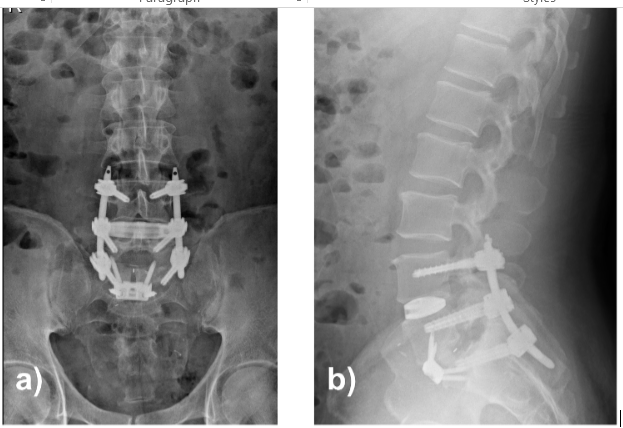

First, an L5–S1 anterior lumbar interbody fusion via a retroperitoneal approach was performed with complete discectomy and placement of a lordotic interbody cage achieving partial reduction of the listhesis. Second, an oblique lumbar interbody fusion at L4–L5 was performed through a left anterolateral approach with cage insertion and grafting. Finally, percutaneous posterior pedicle screw fixation from L4 to S1 was completed in the prone position. Construct alignment and fixation were satisfactory (Fig. 4), and the patient was discharged on post-operative day 3 with no neurological deficits.

Figure 4: Lumbar spine radiographs in anteroposterior (a) and sagittal (b) projections. Solid fixation and restoration of the sagittal alignment are observed.